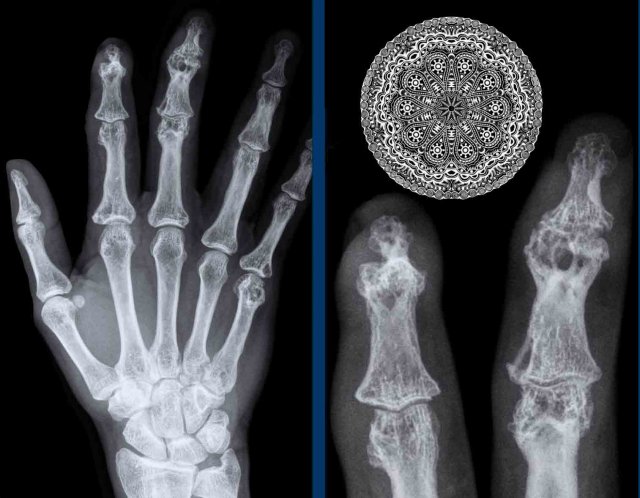

Sausage digits and pencil in cup deformity in Psoriatic arthritis Sausage digits and pencil in cup deformity in Psoriatic arthritis

Sausage digits

Typical appearance of dactylitis “sausage digits” with soft tissue swelling and pencil-in-cup deformity of DIP 1-2 and 5 of the left hand in a patient with psoriatc arthritis.

Notice that the MCP joints are not involved (unlike in RA).

Psoriatic arthritis Psoriatic arthritis

Progressive psoriatic arthritis

1. The picture on the left shows marginal erosions (black arrow) and subtle bone formation (blue arrow) of the IP joint.

2. Later on, it progresses to the typical pencil-in-cup deformation.

The distribution and the bone formation makes the diagnosis of rheumatoid arthritis unlikely.

The marginal erosions and the absence of DIP involvement in other joints makes the diagnosis of erosive osteoarthritis unlikely, although pencil-in-cup can look like the gullwing deformity in erosive osteoarthritis.

Pencil in cup deformity

A. Pencil in cup deformity of 1st and 5th toe.

B. Acro-osteolysis with resorption of the terminal tuft of digits 2-4 and 5.

There are erosions in MTP 2 and 3.